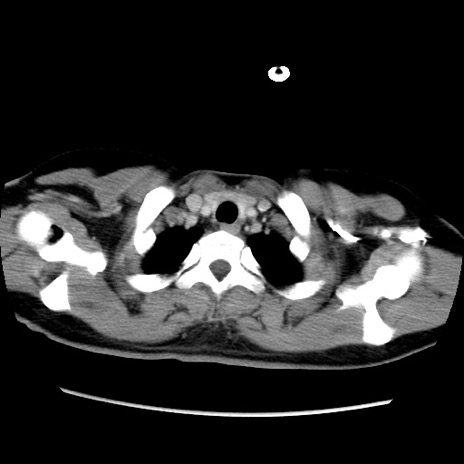

症例39(横断像)

【症例】40歳代女性

【主訴】上下腹部痛

【現病歴】2日目から下腹部痛あり。夜間は痛みで眠れなかった。昨日より上腹部痛と下痢が出現。臥位で痛みは軽快したため、休んでいた。本日になって臥位でも立位でも痛みが強くなってきたため救急要請。

【既往歴】子宮内膜症

【身体所見】部:平坦・軟、左上下腹部に圧痛あり、反跳痛あり。

【データ】WBC 21800、CRP 26.78